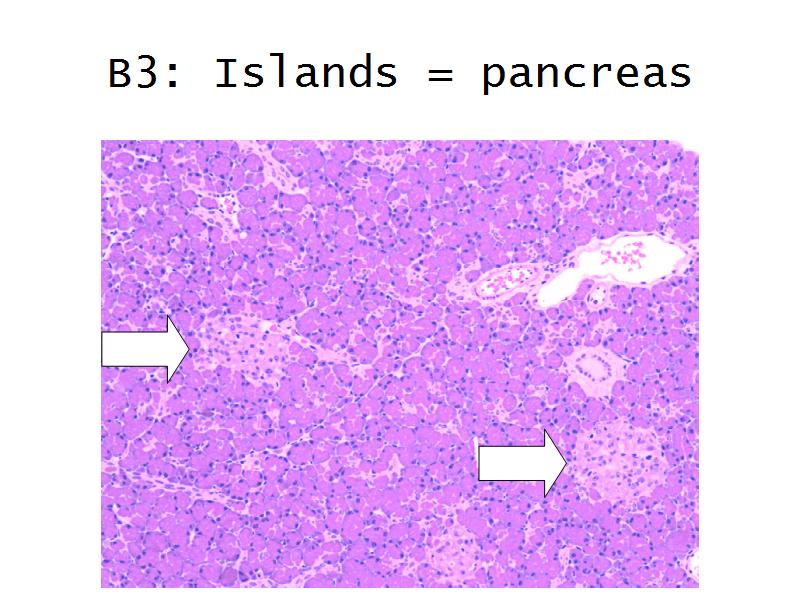

- Pancreas

Question B1 to B4

For each of the following 4 slides

Which gland is arranged as:

- C3: Pancreas = glucagon, insulin, somatostatin, pancreatic polypeptide

- C4:Thyroid gland = thyroxine, triiodothyronine

- F4: Alpha cells = pancreas

- Slide 50: Pancreas